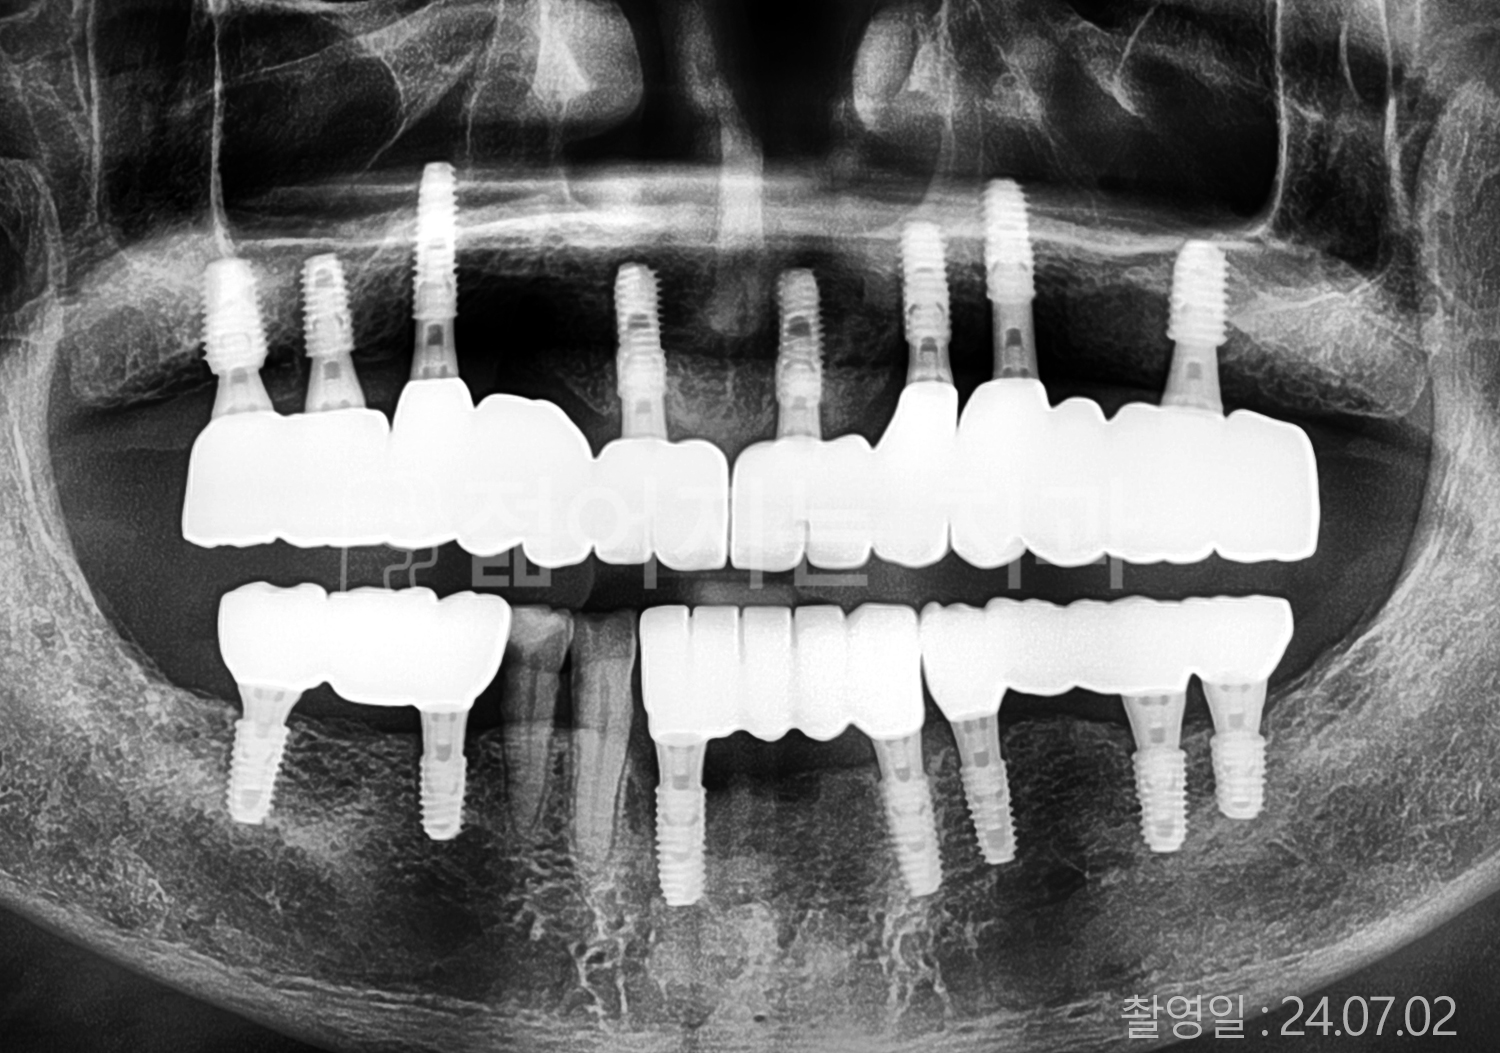

• 70대 고혈압, 당뇨 전체치아 10개 이상 임플란트

• 50대 고혈압, 당뇨 전체치아 10개 이상 임플란트

• 60대 고혈압, 당뇨 전체치아 10개 이상 임플란트

• 50대 전체치아 10개 이상 임플란트

• 70대 당뇨 전체치아 10개 이상 임플란트

• 80대 전체치아 10개 이상 임플란트

• 40대 전체치아 10개 이상 임플란트

• 60대 고협압, 고지혈증 전체치아 10개 이상 임플란트

• 60대 전체치아 10개 이상 임플란트